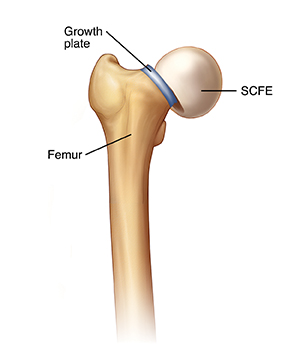

Your child has been diagnosed with a condition called slipped capital femoral epiphysis (SCFE). This means that the femoral head (the ball at the top of the thighbone) has slipped slightly off the thighbone. (It may help to picture a scoop of ice cream slipping off of a cone.) This problem can be very serious if not treated. Your child will likely be referred to an orthopedist, a healthcare provider specializing in treating bone and joint problems, for evaluation and treatment.

Treating SCFE is considered urgent because further slipping could damage the hip joint. To prevent further slipping, the child may be admitted to the hospital right away for surgery. Or the child may be instructed to use crutches and not put any weight on the leg until the SCFE can be fixed. Surgery is often done within 1 or 2 days of diagnosis. During the surgery, the surgeon puts a steel screw through the thighbone into the femoral head. This screw holds the femoral head firmly in place.

In rare cases, even with treatment, the hip joint can still have problems. This is more likely if the growth plate was injured by the slip. The growth plate is a soft part of a long bone that allows the bone to grow as the child grows. Disruption of the blood supply to the femoral head during the slip may also lead to problems. Problems are more likely with severe SCFE. Catching these problems early is one reason why it's vital to continue to follow up with the surgeon as your child grows.